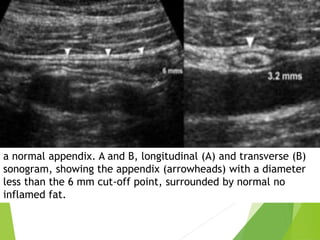

a normal appendix. A and B, longitudinal (A) and transverse (B)

sonogram, showing the appendix (arrowheads) with a diameter

less than the 6 mm cut-off point, surrounded by normal no

inflamed fat.